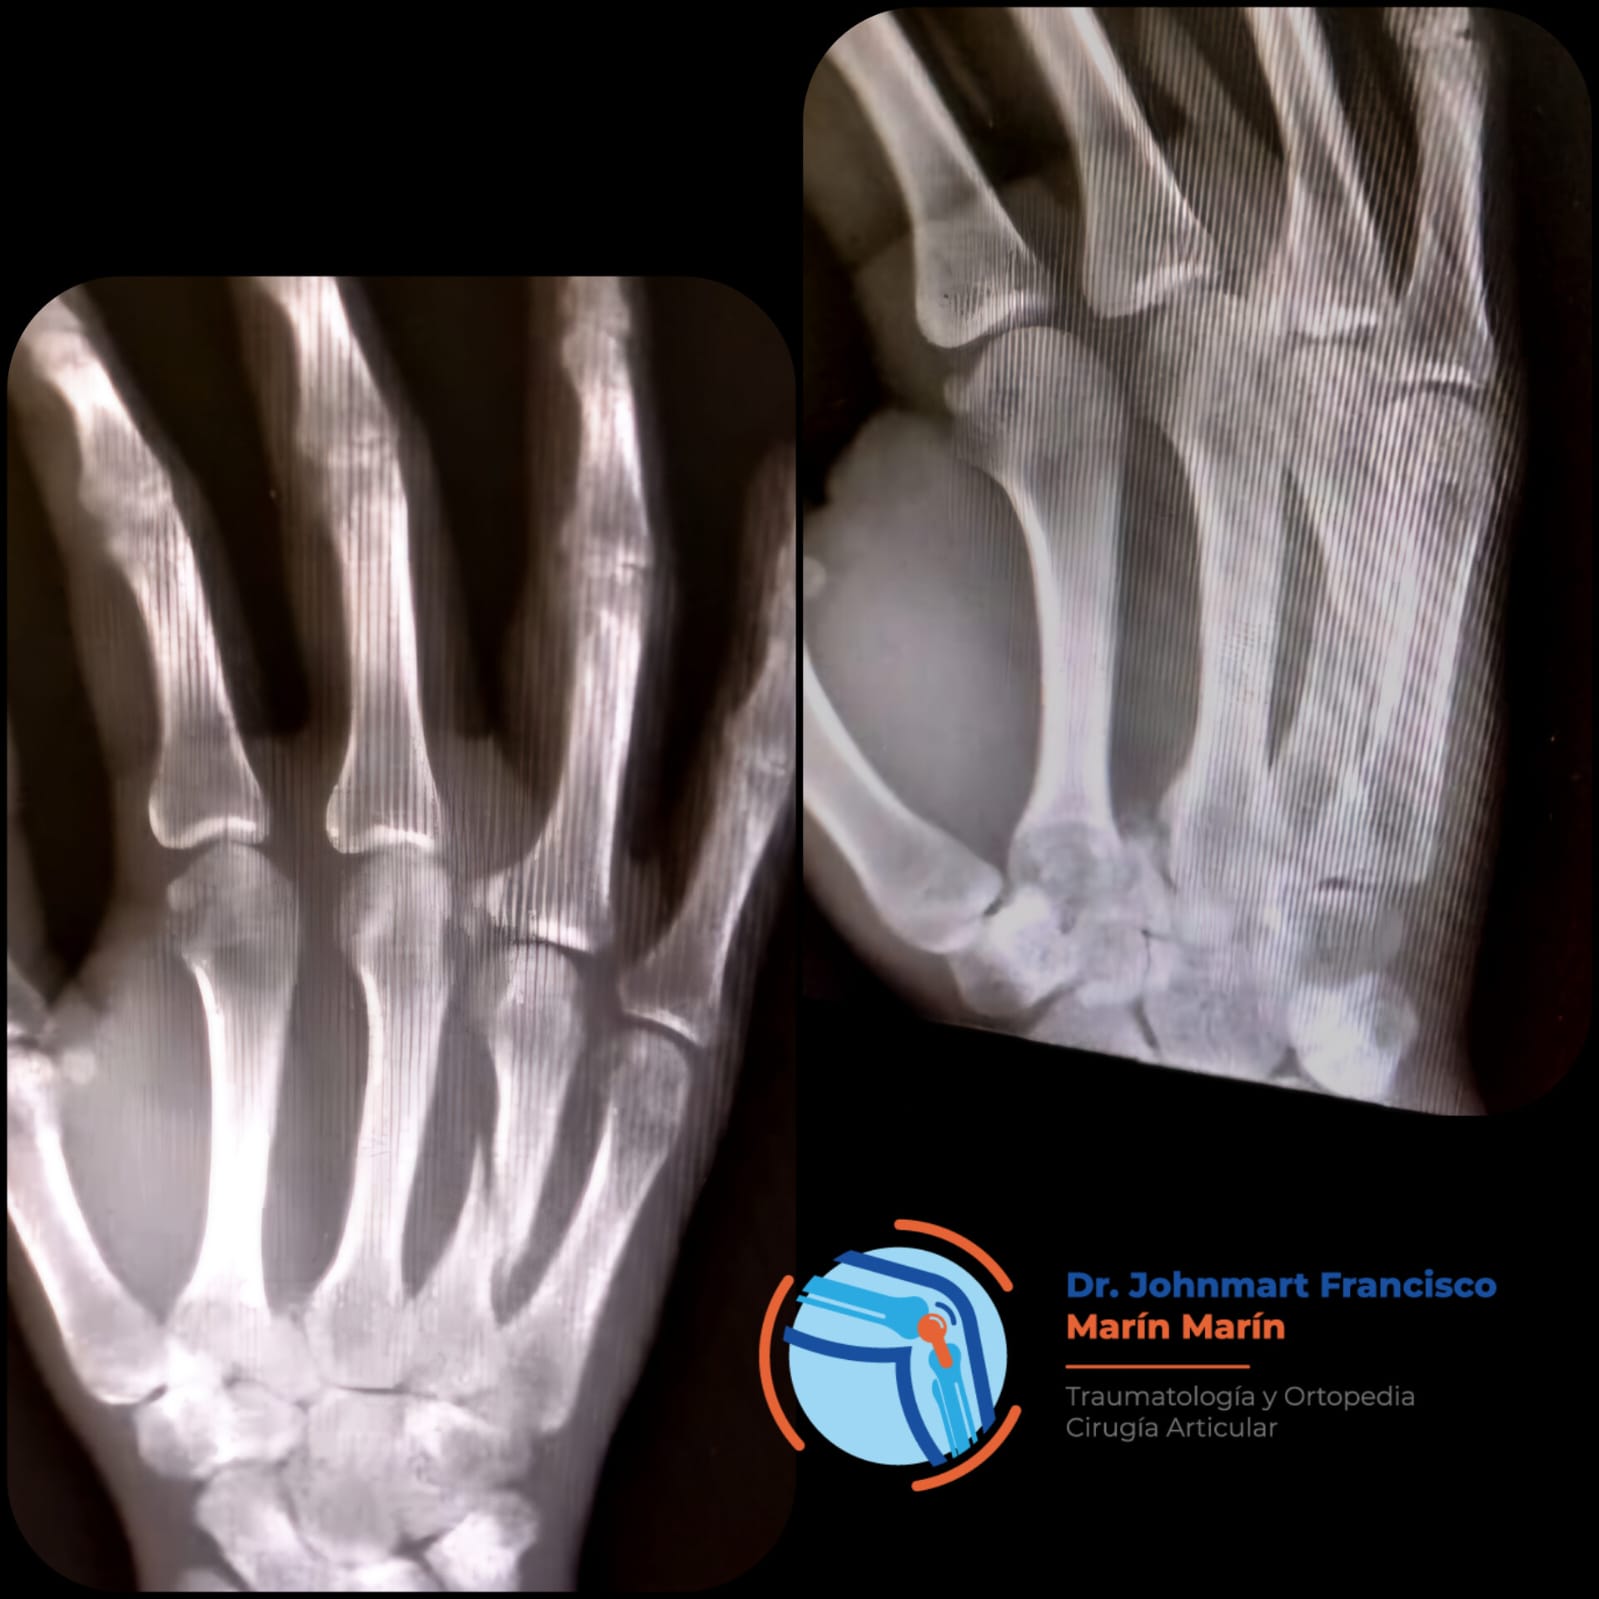

ARTROSCOPIA

Procedimiento quirúrgico, el cual se realiza principalmente en hombro, muñeca, cadera, rodilla, tobillo.